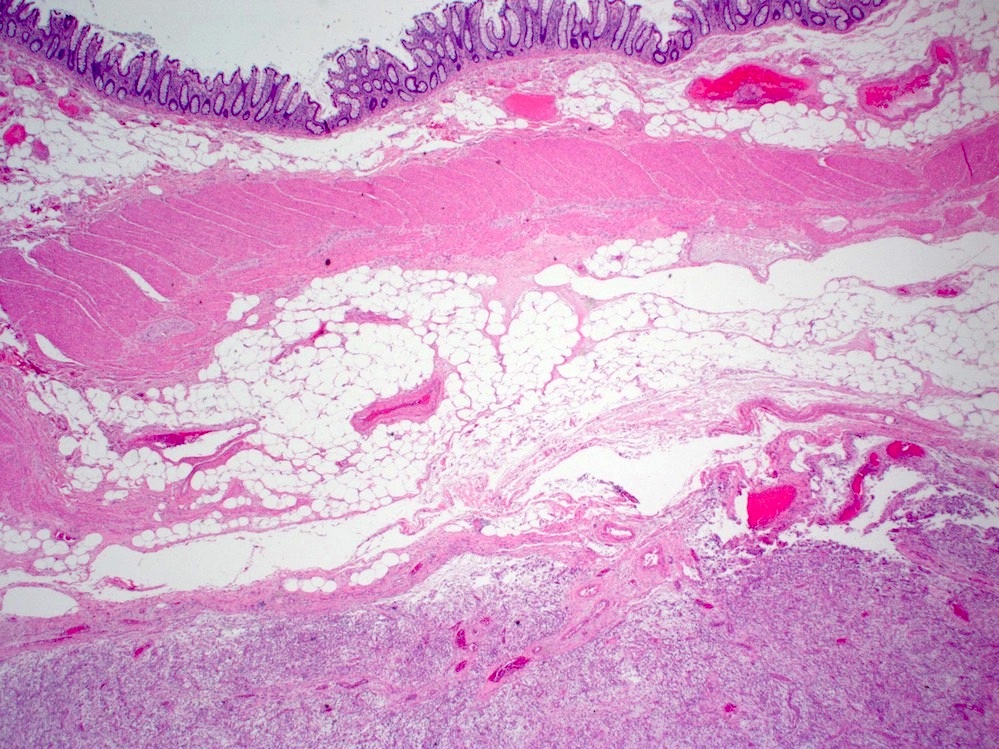

Microscopic (histologic) description

- Bland spindle cells with abundant amphophilic cytoplasm and variably prominent nucleoli

- Lymphoplasmacytic infiltrate with polyclonal plasma cells

- Background may show myxoid change or laminated / whorled fibrosis

- Epithelioid inflammatory myofibroblastic sarcoma: similar, except cells are more epithelioid, with large nucleoli

Microscopic (histologic) images

Contributed by Raul S. Gonzalez, M.D.